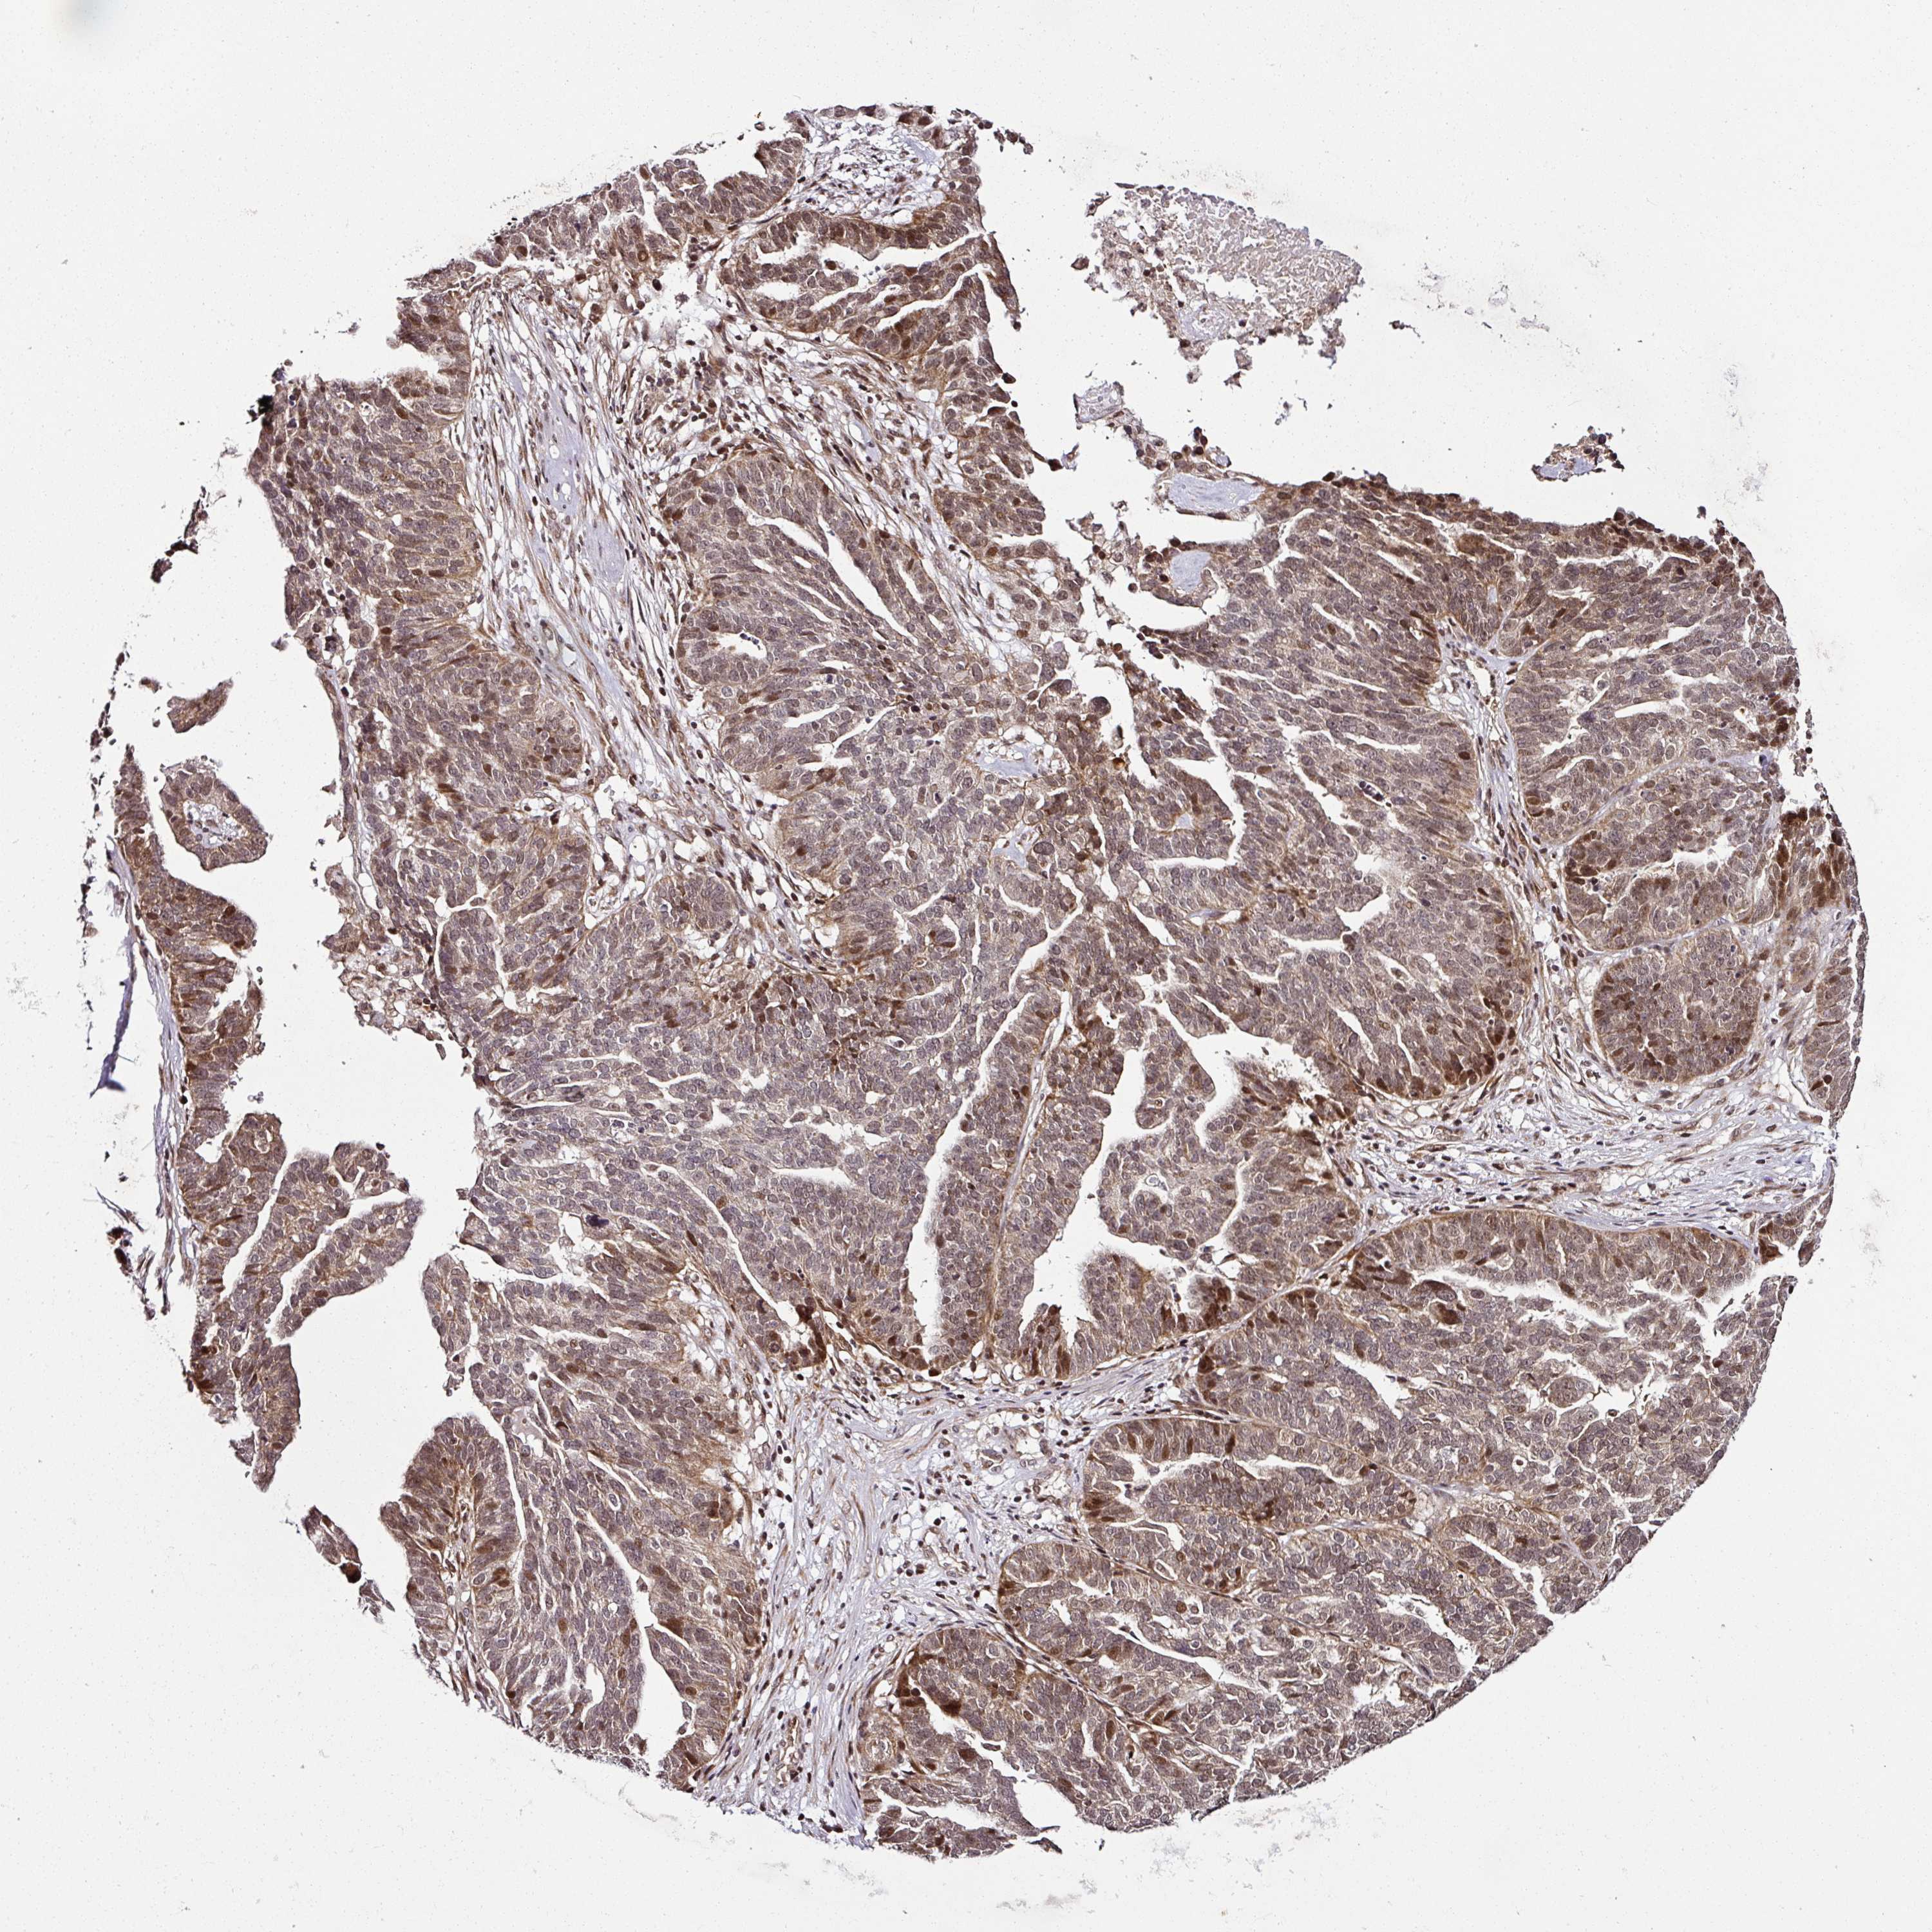

OVARIAN CANCER - Protein expressioni

A mouse-over function shows sample information and annotation data. Click on an image to view it in a full screen mode. Samples can be filtered based on level of antibody staining by selecting one or several of the following categories: high, medium, low and not detected. The assay and annotation is described here.

Note that samples used for immunohistochemistry by the Human Protein Atlas do not correspond to samples in the TCGA dataset.

Antibody stainingi

Antibody staining in the annotated cell types in the current human tissue is reported as not detected, low, medium, or high, based on conventional immunohistochemistry profiling in selected tissues. This score is based on the combination of the staining intensity and fraction of stained cells.

Each image is clickable and will lead to virtual microscopy that enables deeper exploration of all samples and also displays staining intensity scores, fraction scores and subcellular localization as well as patient and tissue information for each sample.

Antibody HPA052552

Staining

High

Medium

Low

Not detected

Intensity

Strong

Moderate

Weak

Negative

Quantity

>75%

75%-25%

<25%

None

Location

Nuclear

Cytoplasmic/membranous

Cytoplasmic/membranous,nuclear

Cystadenocarcinoma, serous, NOS

Carcinoma, NOS

Cystadenocarcinoma, mucinous, NOS

Carcinoma, endometroid